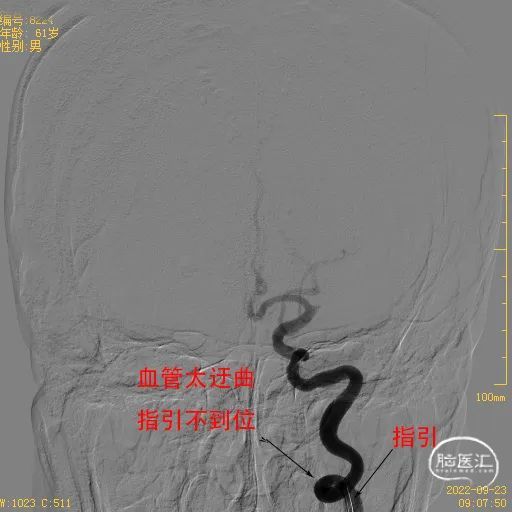

①右侧股动脉穿刺成功后,8F指引导管建立通路,颈内动脉太过迂曲,指引不到位,只能到达C1近端,置入115cm 5F Catalyst 5中间管至床突段提供支撑。

采用8F指引+5F 115cm Catalyst5导管建立稳定的通路。